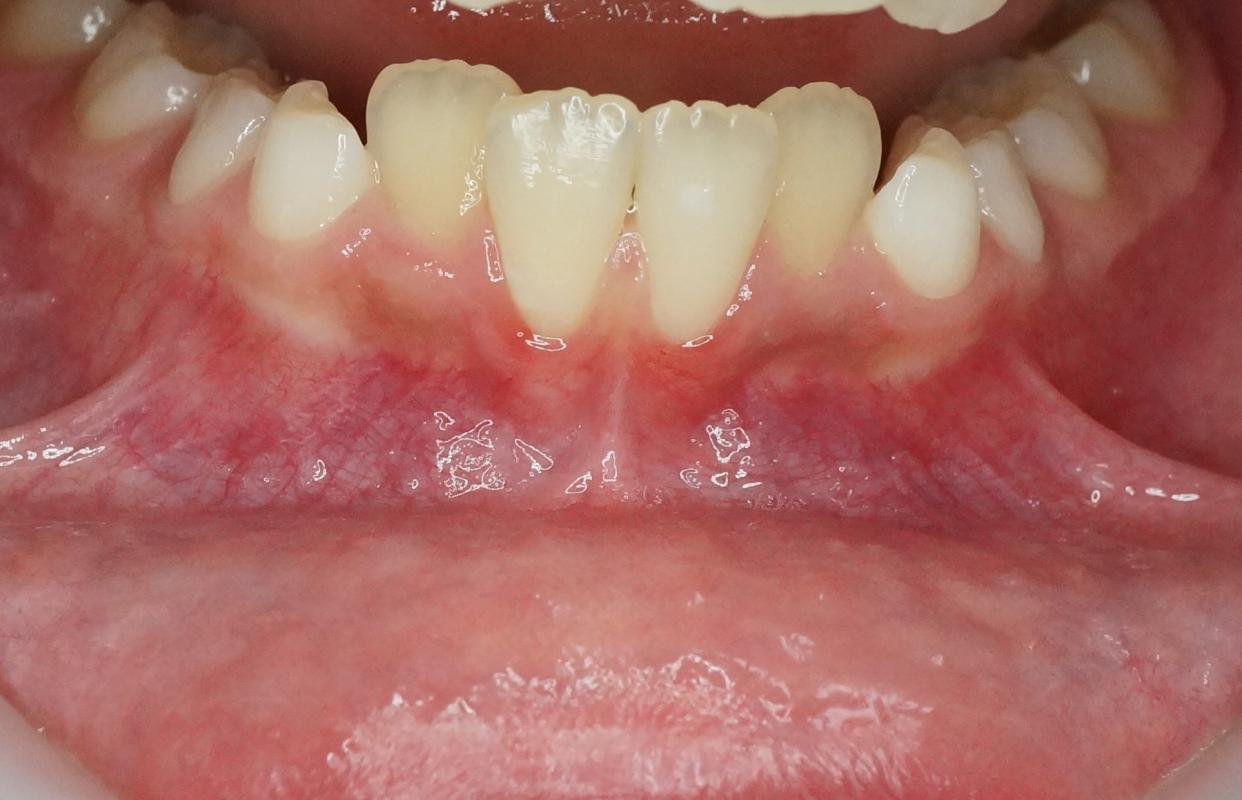

- Parodonte fin avec hauteur de gencive attachée réduite voire récessions (figure 4d)

Figure 4 : patiente de 9 ans présentant un déséquilibre mécanique de la région incisivo-canine mandibulaire se traduisant par un sillon labio-mentonnier marqué (a) avec empreinte cutanée (b), une rétroalvéolie mandibulaire globale (c) et un parodonte affaibli avec profondeur vestibulaire réduite (d).

Figure 5 : patiente de 38 ans présentant un déséquilibre mécanique de la région incisivo-canine mandibulaire se traduisant par un encombrement incisivo-canin sévère par rétroalvéolie et égression incisive (a), un parodonte fin et une muqueuse libre suivant le relief des racines des incisives (b), et une absence d’os alvéolaire vestibulaire au CBCT (c, d et e).